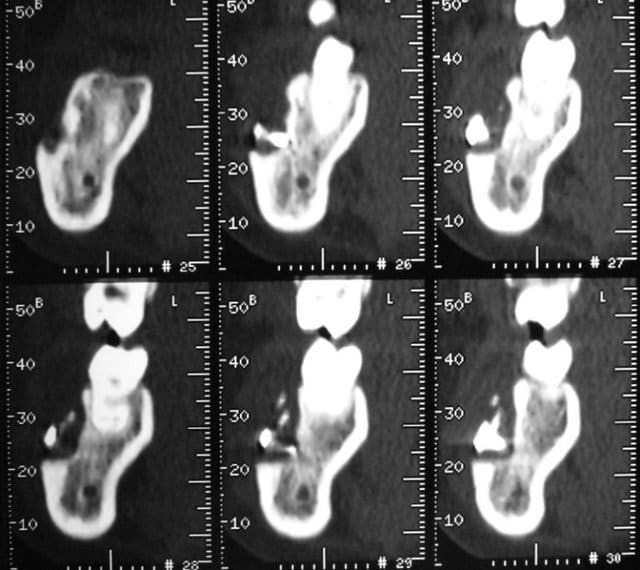

Il semble bien que la radio (et les coupes scan) que tu présentes appartiennent à un cas de traumatologie ou de chirurgie orthognathique. Ce ne sont certes pas des ancrages orthodontiques. Ne mélangeons pas tout, svp ! (à moins que ce ne soit de la provocation ou de la mauvaise foi, cher Bjc, mais je n'ose quand même pas penser cela de ta part).

Puisque j'ai eu la chance ( moi et non pas le patient) d'etre confronté à cette situation, je l'ai pris pour éxemple, pour montrer que ces techniques ne sont pas éxemptes de risques. Tout comme l'anesthésie intra-osseuse.

C'est un cas extrème, certes, mais ce sont les plus parlants.

Cas extrême ? J’ai mieux que cela (fig. jointes).

Ami d’Eugénol qui lis ces lignes, rassure-toi ! Ce sont des cas de chirurgie maxillo-faciale qui n’ont rien à voir avec les cas d’ancrages osseux orthodontiques, ni avec la discussion en cours. Notre bon Bjc a introduit cet aparté car il aime bien les facéties.